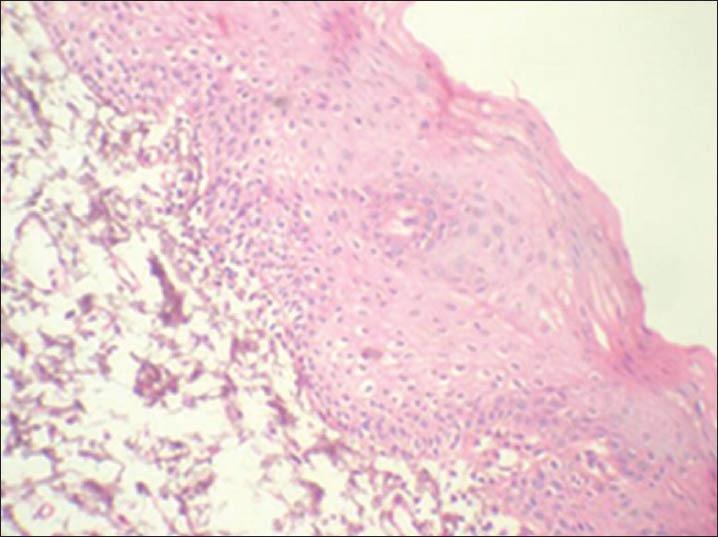

To look for its immunohistochemical expression in clinically normal mucosa from patients with and without tobacco habits, leukoplakia; and correlate its expression to individual atypical morphologic features, as seen in hematoxylin and eosin (H and E) sections of leukoplakia exhibiting dysplasia.

研究细胞周期蛋白质D1在有或无吸烟习惯患者的临床正常黏膜、白斑中免疫组化表达情况;并将其表达与个体非典型形态学特征相关联,这些特征可见于显示发育异常的白斑苏木精和伊红(H&E)切片中。